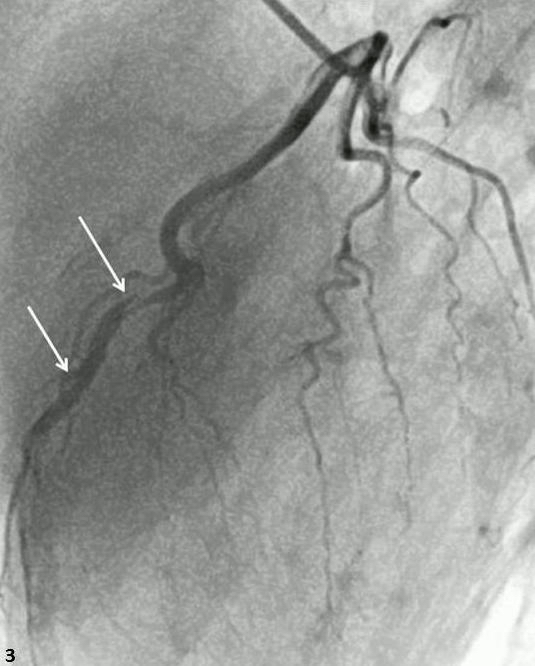

Abstract PDF ECG 1 Angio 1 Angio 2 Angio 3 Angio 4 ECG 2 Table Chart Original File 1 2 3 4 5 6 Reply to reviewer Fig. 1. ECG during myocardial infarction Fig. 2. Coronary angiography of LCA during myocardial infarction Fig. 3. Coronary angiography of LCA during myocardial infarction Fig. 3a. Coronary angiography of LCA during myocardial infarction Fig. 4. Coronary angiography of LCA 2 years after myocardial infarction Fig. 5. Coronary angiography of LCA 2 years after myocardial infarction Fig. 6. ECG 2 years after myocardial infarction Fig. 7. Thrombolytic trials in patients with coronary artery dissection Fig. 8. Flow chart of the study selection process -

Successful primary percutaneous coronary interventions in a patient with two consecutive ST-segment elevation myocardial infarctions and dual left anterior descending artery (type IV)